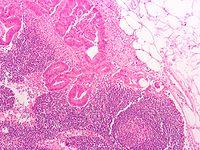

Subdivisions

A lymph node is divided into compartments called nodules (or lobules), each consisting of a region of cortex with combined follicle B cells, a paracortex of T cells, and a part of the nodule in the medulla.[14] The substance of a lymph node is divided into the outer cortex and the inner medulla.[3] The cortex of a lymph node is the outer portion of the node, underneath the capsule and the subcapsular sinus.[14] It has an outer part and a deeper part known as the paracortex.[14] The outer cortex consists of groups of mainly inactivated B cells called follicles.[2] When activated, these may develop into what is called a germinal centre.[2] The deeper paracortex mainly consists of the T cells.[2] Here the T-cells mainly interact with dendritic cells, and the reticular network is dense.[15]

The medulla contains large blood vessels, sinuses and medullary cords that contain antibody-secreting plasma cells. There are fewer cells in the medulla.[2]

The medullary cords are cords of lymphatic tissue, and include plasma cells, macrophages, and B cells.

Cells

In the lymphatic system a lymph node is a secondary lymphoid organ.[2] Lymph nodes contain lymphocytes, a type of white blood cell, and are primarily made up of B cells and T cells.[2] B cells are mainly found in the outer cortex where they are clustered together as follicular B cells in lymphoid follicles, and T cells and dendritic cells are mainly found in the paracortex.[16]

There are fewer cells in the medulla than the cortex.[2] The medulla contains plasma cells, as well as macrophages which are present within the medullary sinuses.[16]